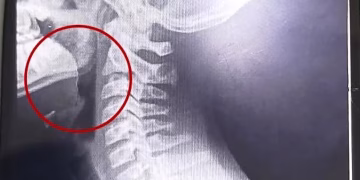

El Schestakow puso nuevamente en marcha el tomógrafo y sumó dos respiradores